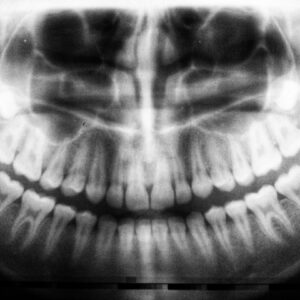

Tooth Decay In Kids

Tooth decay, also known as dental caries, is a prevalent issue among children that can lead to significant health problems if left untreated. As a parent or caregiver, it’s essential…